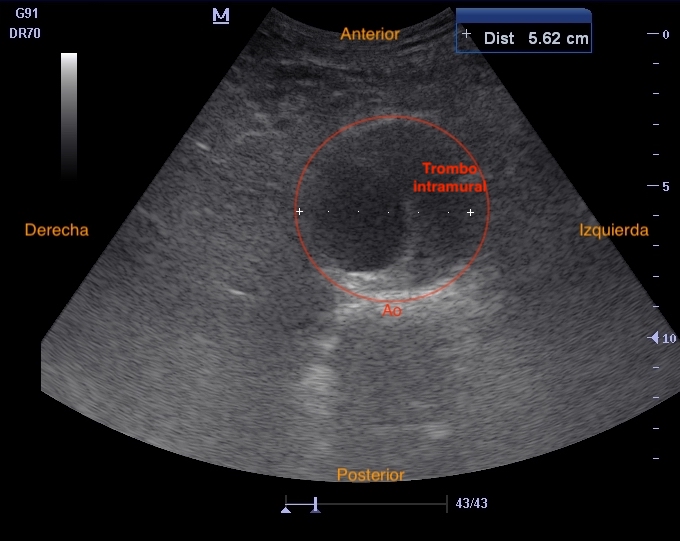

• Motivo de ecografía: control diámetro de aneurisma aórtico abdominal y valoración de signos de rotura.

Hallazgos ecográficos

Realizamos eco en consulta donde se aprecia el AAA de 5,6 cm con trombo mural similar a previo, sin signos de rotura.

Aneurisma aórtico abdominal infrarrenal de > 5,5 cm con trombo intramural en su interior.